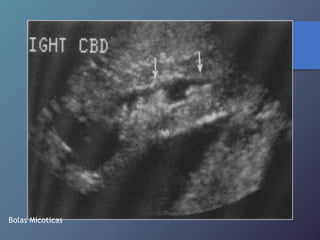

LESION EN DIANA (CANDIDIASIS)

Bolas Micoticas

Enfermedades Micoticas Hepáticas • Infecciónsecundaria hepática por diseminación Hematógena de micosis sistémicas (cándidas). • Inmunosuprimidos. • Ecográficamente lesión en forma de ojo de toro (Centro hiperecoico Y anillo hipoecoico), diámetro De 1-4cm. • Uniformemente hipoecoica (frecuente por fibrosis Progresiva). • Ecogena: calcificación variable por formación de Cicatriz.

LESION EN DIANA(CANDIDIASIS)